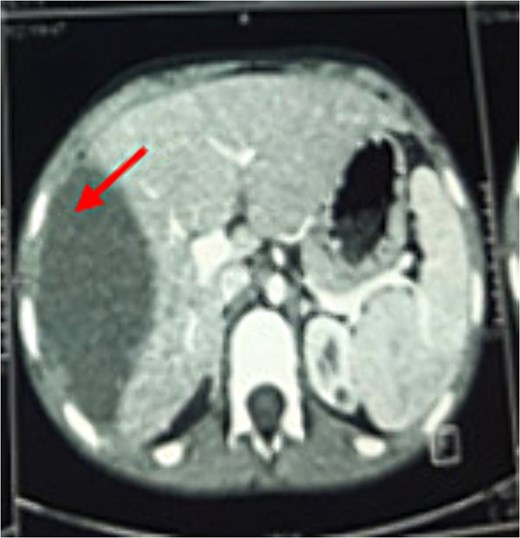

A laparotomy via a right subcostal incision was performed. Exploration identified a unilocular, non-adherent hydatid cyst localized solely to the diaphragm, without adherence to the lung or abdominal viscera (Fig. 3a and b). A cystotomy was performed with the removal of multiple daughter vesicles. The pericyst cavity was excised, and the diaphragmatic defect was repaired. Intraoperative inspection confirmed diaphragmatic integrity and no lung involvement. A histopathological examination confirmed the diagnosis of HD. Postoperatively, the patient received oral mebendazole for 8 weeks, commencing on the first postoperative day. Three months of follow-up showed no clinical or radiological signs of recurrence.

Intraoperative findings. (a) Location of the DHC during resection without adherence to the lung or abdominal viscera. (b) Germinative membrane of the DHC.